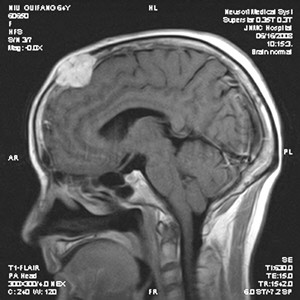

顱骨骨瘤是一種生長緩慢的良性骨腫瘤,與周圍顱骨分界常不清楚,可以發(fā)生于顱骨的任何部位。常見單發(fā),但亦有多發(fā)或聚發(fā)于一處者。青中年好發(fā)。瘤體較小者一般無自覺癥狀,較大者局部輕微脹痛或麻木感,體檢局限腫塊,基底寬,表面光滑與頭皮無粘連,無壓痛。位于顱底或鼻竇處,出現(xiàn)腦神經(jīng)受累癥狀及鼻塞。生長緩慢無癥狀的小骨瘤,可予觀察處理;生長較快,瘤體大及有腦受壓癥狀者,手術(shù)治療。腫瘤切除后顱骨缺損范圍大者同期行修補(bǔ)術(shù)。無特效藥物治療,手術(shù)者,術(shù)后使用抗生素治療一周左右。

顱骨骨瘤是一種常見的良性腫瘤,特點(diǎn)是生長緩慢、不痛、廣基,與周圍顱骨分界常不清楚?梢园l(fā)生于顱骨的任何部位,以額骨和頂骨...【詳細(xì)】

顱骨骨瘤是一種常見的良性腫瘤,特點(diǎn)是生長緩慢、無痛、廣基,與周圍顱骨分界常不清楚?梢园l(fā)生于顱骨的任何部位,以額骨和頂骨...【詳細(xì)】